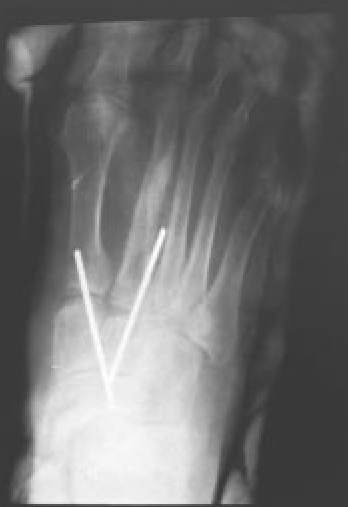

Fig. 5B.: Control postoperatorio tras reducción abierta y osteosíntesis con agujas de Kirschner